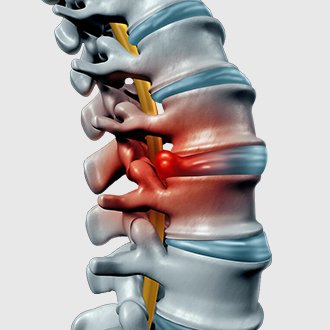

Bác sỹ Mỹ dùng kỹ thuật nắn chỉnh Chiropractic để xác định chính xác các sai lệch trên cột sống và điều chỉnh các sai lệch dù là nhỏ nhất về đúng vị trí, giải phóng các áp lực lên cột sống, đĩa đệm và rễ thần kinh. Từ đó, giúp loại bỏ cơn đau nhanh chóng, phục hồi đĩa đệm và đốt sống bị tổn thương, kích thích cơ chế tự chữa lành của cơ thể. Qua đó, giúp điều trị tận gốc căn nguyên gây bệnh.

- Thoát vị đĩa đệm

- Phình lồi đĩa đệm